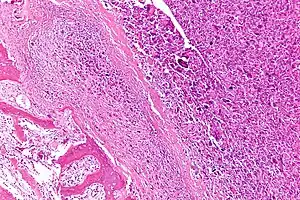

| Intermediate-magnification micrograph of an osteosarcoma (center and right of image) adjacent to non-malignant bone (left-bottom of image): The top-right of the image has poorly differentiated tumor. Osteoid with a high density of malignant cells is seen between the non-malignant bone and poorly differentiated tumor (H&E stain). | |

Microscopically: The characteristic feature of osteosarcoma is presence of osteoid (bone formation) within the tumor. Tumor cells are very pleomorphic (anaplastic), some are giant, numerous atypical mitoses. These cells produce osteoid describing irregular trabeculae (amorphous, eosinophilic/pink) with or without central calcification (hematoxylinophilic/blue, granular)—tumor bone. Tumor cells are included in the osteoid matrix. Depending on the features of the tumor cells present (whether they resemble bone cells, cartilage cells, or fibroblast cells), the tumor can be subclassified. Osteosarcomas may exhibit multinucleated osteoclast-like giant cells.[21]